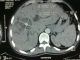

A fifty-year-old male with no special note of past or social history presented with high-grade fever and right hypochondrial pain of two week duration. The patient was jaundiced, febrile and had a tender hepatomegaly just below right costal. Investigations showed a deranged liver function test (LFT) with a total bilirubin of 258,40mg/dl, AST(420 U/L), ALT(415 U/L), G.G.T(328 UI/L) and raised serum alkaline phosphatase(1181 U/L). Hydatid serology was positive. CT scan revealed intraparenchymic hydatid cyst type IV(4th and 5th segments) that opened totally into common bile duct (Figure 1 , Figure 2).

Figure 1 : abdominal

CT showing hydatid cyst of 4th & 5th segments of liver communicating wit

dilated CBD

Figure 2: abdominal CT

showing hydatid cyst of 4th & 5th segments of liver communicating wit dilated

CBD